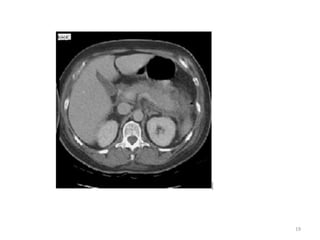

TC DE ABDOME:

Entre o 3 e 10 dias de evolução,

com contraste para evidenciar:

•INFLAMAÇÃO PERIPANCREATICA.

•COLEÇÕES PERIPANCREATICAS.

•DETERMINAR EXISTENCIA,

LOCALIZAÇÃO E TAMANHO DA

NECROSE PANCREATICA

O GRAU DE INFLAMAÇÃO PERIPANCREATICA, SE EVIDENCIA NOS

CRITERIOS DE BALTHAZAR